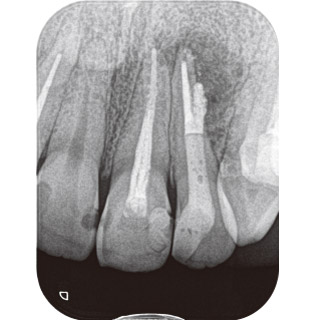

症例2-1 初診時X線写真。サイナストラクトが消えないとのことで近医より紹介。歯髄の診断は既根管治療歯、根尖周囲組織の診断は症状のある根尖性歯周炎ならびに慢性根尖膿瘍と診断し、2の再根管治療の必要性を説明し、治療開始。 -

症例2-2 サイナストラクトよりガッタパーチャポイントを挿入しX線撮影。 -

症例2-3 外傷の既往もあるとのことでCBCT撮影。頰側へのパーフォレーションも確認できる。 -